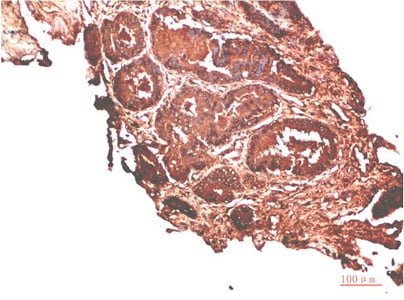

IHC (Immunohistochemistry)

The ATM atm (Catalog #AAA293814) is an Antibody produced from Rabbit and is intended for research purposes only. The product is available for immediate purchase. The ATM Rabbit Polyclonal Antibody reacts with Human, Mouse, Rat and may cross-react with other species as described in the data sheet. AAA Biotech's ATM can be used in a range of immunoassay formats including, but not limited to, IHC (Immunohistochemistry). Researchers should empirically determine the suitability of the ATM atm for an application not listed in the data sheet. Researchers commonly develop new applications and it is an integral, important part of the investigative research process. It is sometimes possible for the material contained within the vial of "ATM, Polyclonal Antibody" to become dispersed throughout the inside of the vial, particularly around the seal of said vial, during shipment and storage. We always suggest centrifuging these vials to consolidate all of the liquid away from the lid and to the bottom of the vial prior to opening. Please be advised that certain products may require dry ice for shipping and that, if this is the case, an additional dry ice fee may also be required.Precautions